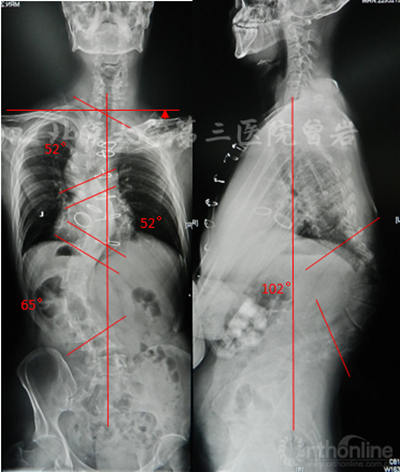

術前X線(圖5):側凸上胸彎Cobb 52°,下胸彎Cobb 52°,胸腰彎Cobb 65°,后凸角度102°,左肩高于右肩。

圖5